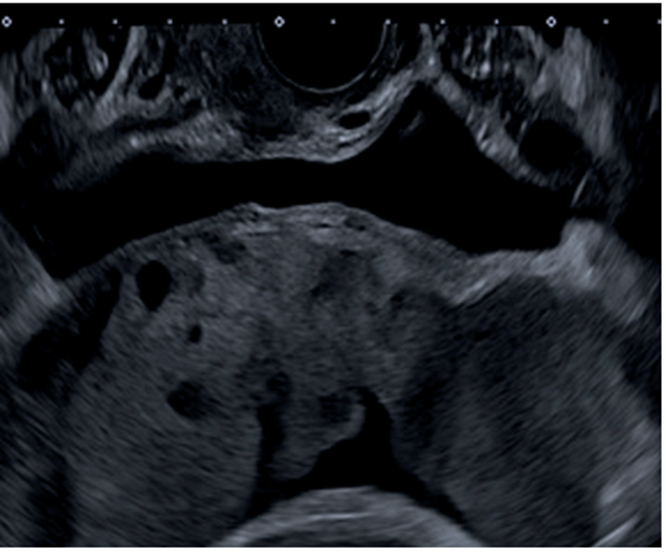

La paciente es valorada inicialmente por la Unidad de Diagnóstico Prenatal del Centro Hospitalario Pereira Rossell, donde cursando un embarazo de 31 semanas de edad gestacional, se realiza la sospecha diagnóstica de acretismo placentario. Se destaca de las imágenes elementos característicos de acretismo, como son, placenta previa oclusiva total con un aumento de su vascularización, pérdida de área hipoecoica retroplacentaria, abundantes lagunas placentarias y pérdida de diferenciación con miometrio en área del segmento (figura 1,figura 2,figura 3).